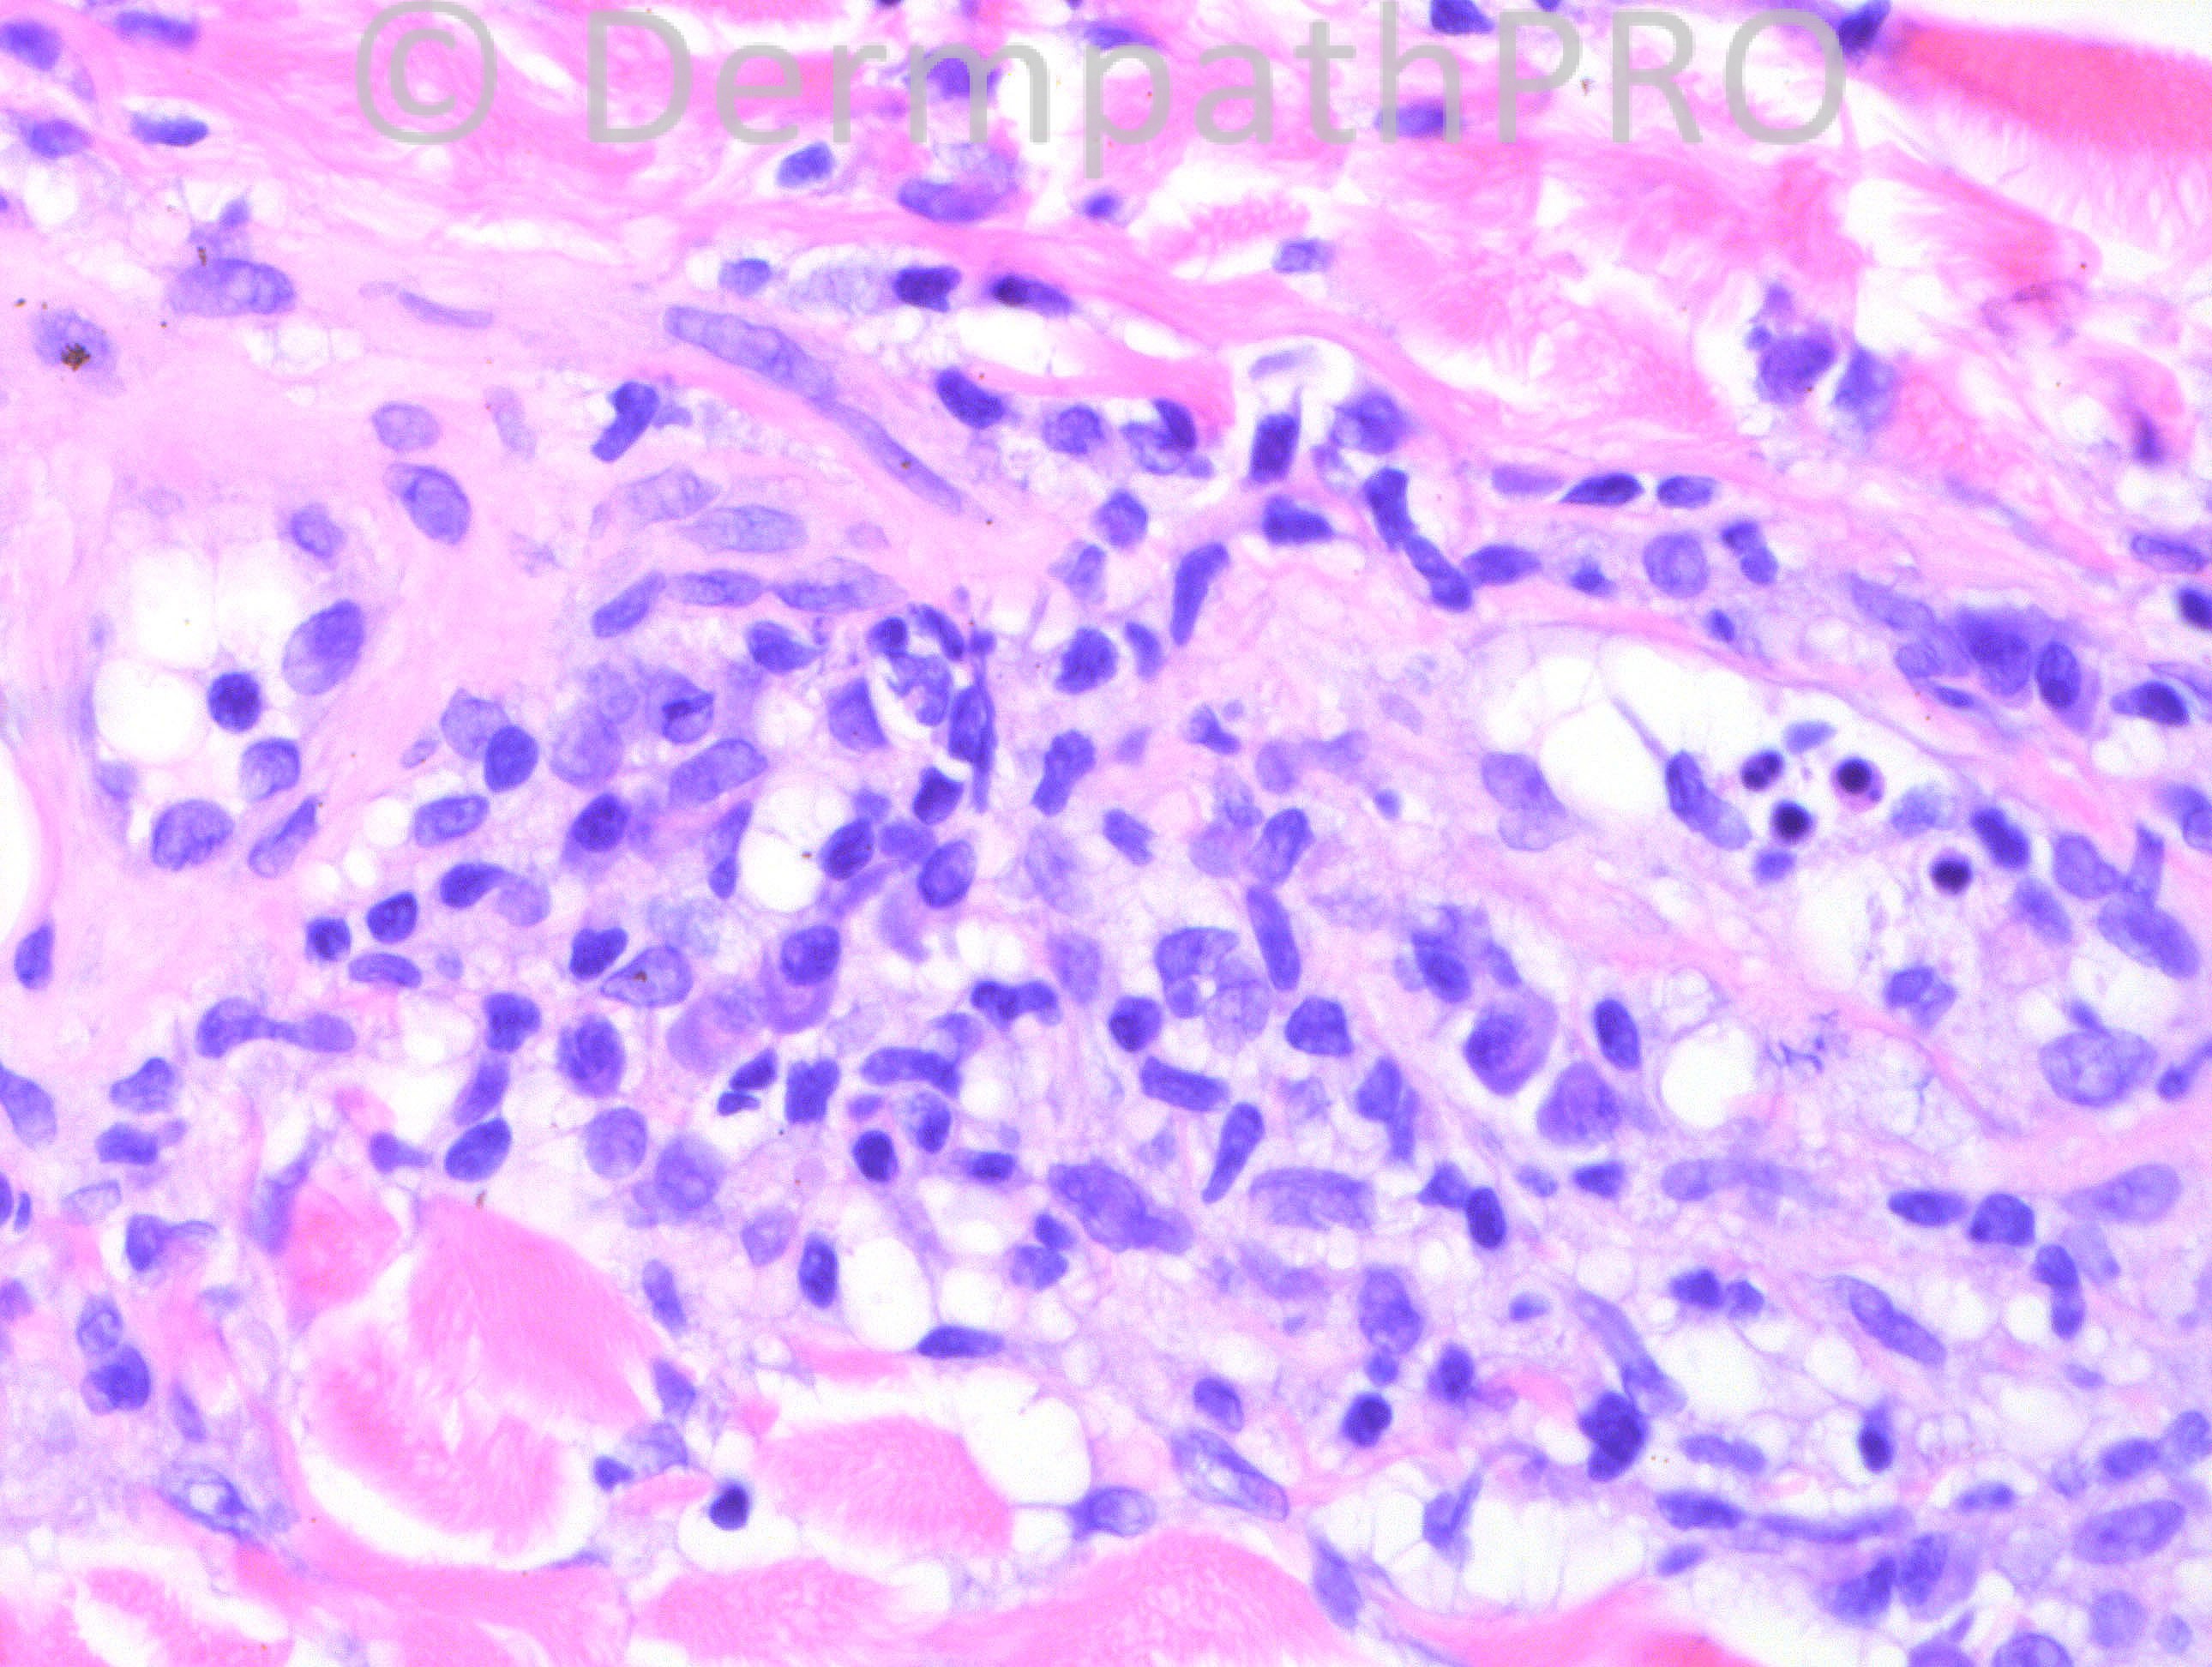

22 years-old female with lesion on shin.